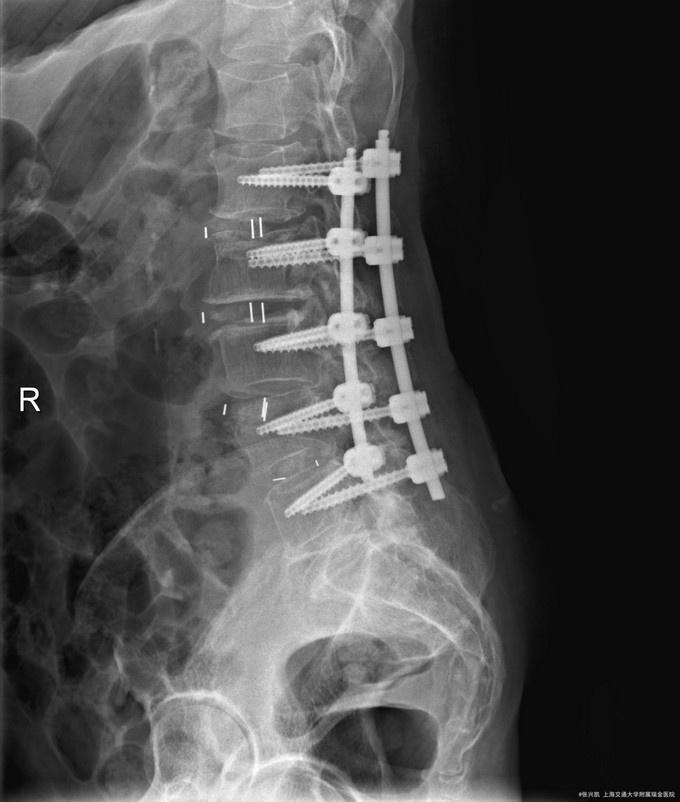

主诉:双下肢麻木7年,腰部酸痛无力 现病史:女性患者,70岁,患者诉腰背无力十几年,约于7年前无明显诱因下出现下肢麻木,站立位加重。后出现腰臀部僵硬,弓背加重,行走距离较短, 不足百米,几年前外院检查诊断为腰椎管狭窄,具体不详。

查体:侧弯畸形,右臀部及右下肢麻木疼痛,腰部活动受限,难以站立。右侧支腿抬高试验50°。双下肢肌力肌张力可。 辅助检查: 磁共振:L1-5,L5-S1腰椎椎间盘突出,腰椎退变,腰椎侧弯

诊断: 腰椎侧弯,腰椎间盘突出 治疗:1期微创侧路椎体融合术+2期 微创后路经皮内固定术

患者侧路微创术后神经压迫症状减轻,腰椎矢状位及冠状位腰椎力线得到改善,戴支具术后可早期下床活动,术后2周后行后路固定手术。